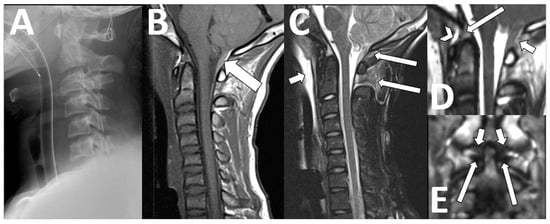

Our contextualized MRI cervical spine protocol for the CCJ includes sagittal T1-weighted images to assess for the presence of diagnostic anatomical features of Chiari I deformity, as well as a 3D heavily T2-weighted sagittal sequence to evaluate restriction of the CSF spaces at the CCJ. We also include a PC CSF flow study, which allows additional evaluation of CSF flow dynamics and abnormal motion of intraspinal contents (Figure 7).

Figure 7. Chiari deformity. An 18-month-old female with new onset seizures and speech delay. Sagittal T1-weighted image shows descent of the cerebellar tonsils ((A), arrow) below the foramen magnum ((A), dotted line) by 8 mm. There was diminished flow across the posterior craniocervical junction ((B), arrow) and abnormal motion of the tonsils ((C), arrow). Follow-up imaging at 4 years of age shows interval suboccipital decompression surgery ((D), short arrow) and improved CSF flow across the craniocervical junction ((E), arrow), as well as resolved abnormal tonsillar motion. A small cervical syrinx persists post-surgically ((D), long arrow).